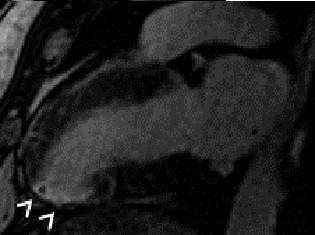

A 42-year-old Tunisian man with congenital hypofibrinogenemia and no cardiovascular risk factors presented with new onset prolonged angina pectoris. An electrocardiogram showed features of inferior acute myocardial infarction. His troponin levels had reached 17 ng/L. Laboratory findings confirmed hypofibrinogenemia and ruled out thrombophilia. Echocardiography was not useful in providing diagnostic elements but did show preserved left ventricular function. Coronary angiography was not performed and our patient did not receive any anticoagulant treatment due to the major risk of bleeding. Magnetic resonance imaging confirmed myocardial necrosis. Our patient was managed with aspirin, a beta-blocker, an angiotensin-converting enzyme inhibitor and statin medication. The treatment was well tolerated and no ischemic recurrence was detected.